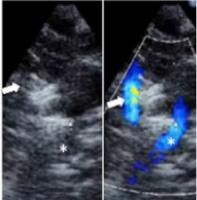

Actualité publiée le 04/06/2024STÉNOSE AORTIQUE : Remplacement valvulaire par cathéter ou chirurgie à cœur ouvert ?

PERSISTANCE du CANAL ARTÉRIEL: Le cathéter pour réparer sans chirurgie les bébés prématurés